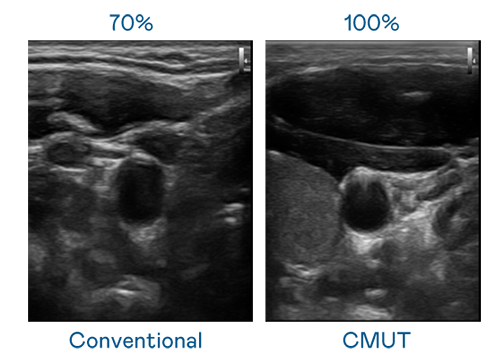

CMUT 技术是一种用电容式微机电元件来产生超音波讯号的技术。与传统 PZT 压电式技术相比,CMUT 频宽增加 30%,更宽频的超音波讯号让影像解析度大幅提升,是实现高影像品质医疗超音波扫描、促进精准医疗发展的关键技术。

超音波影像的解析度高低,首先取决于探头能发出的讯号频宽。CA88 CMUT 可提供高清晰的超音波讯号,提供高频宽、高灵敏度、影像纹理细节更高的超音波影像,协助医护人员缩短影像判读时间及利用精准的医疗影像进行诊断。